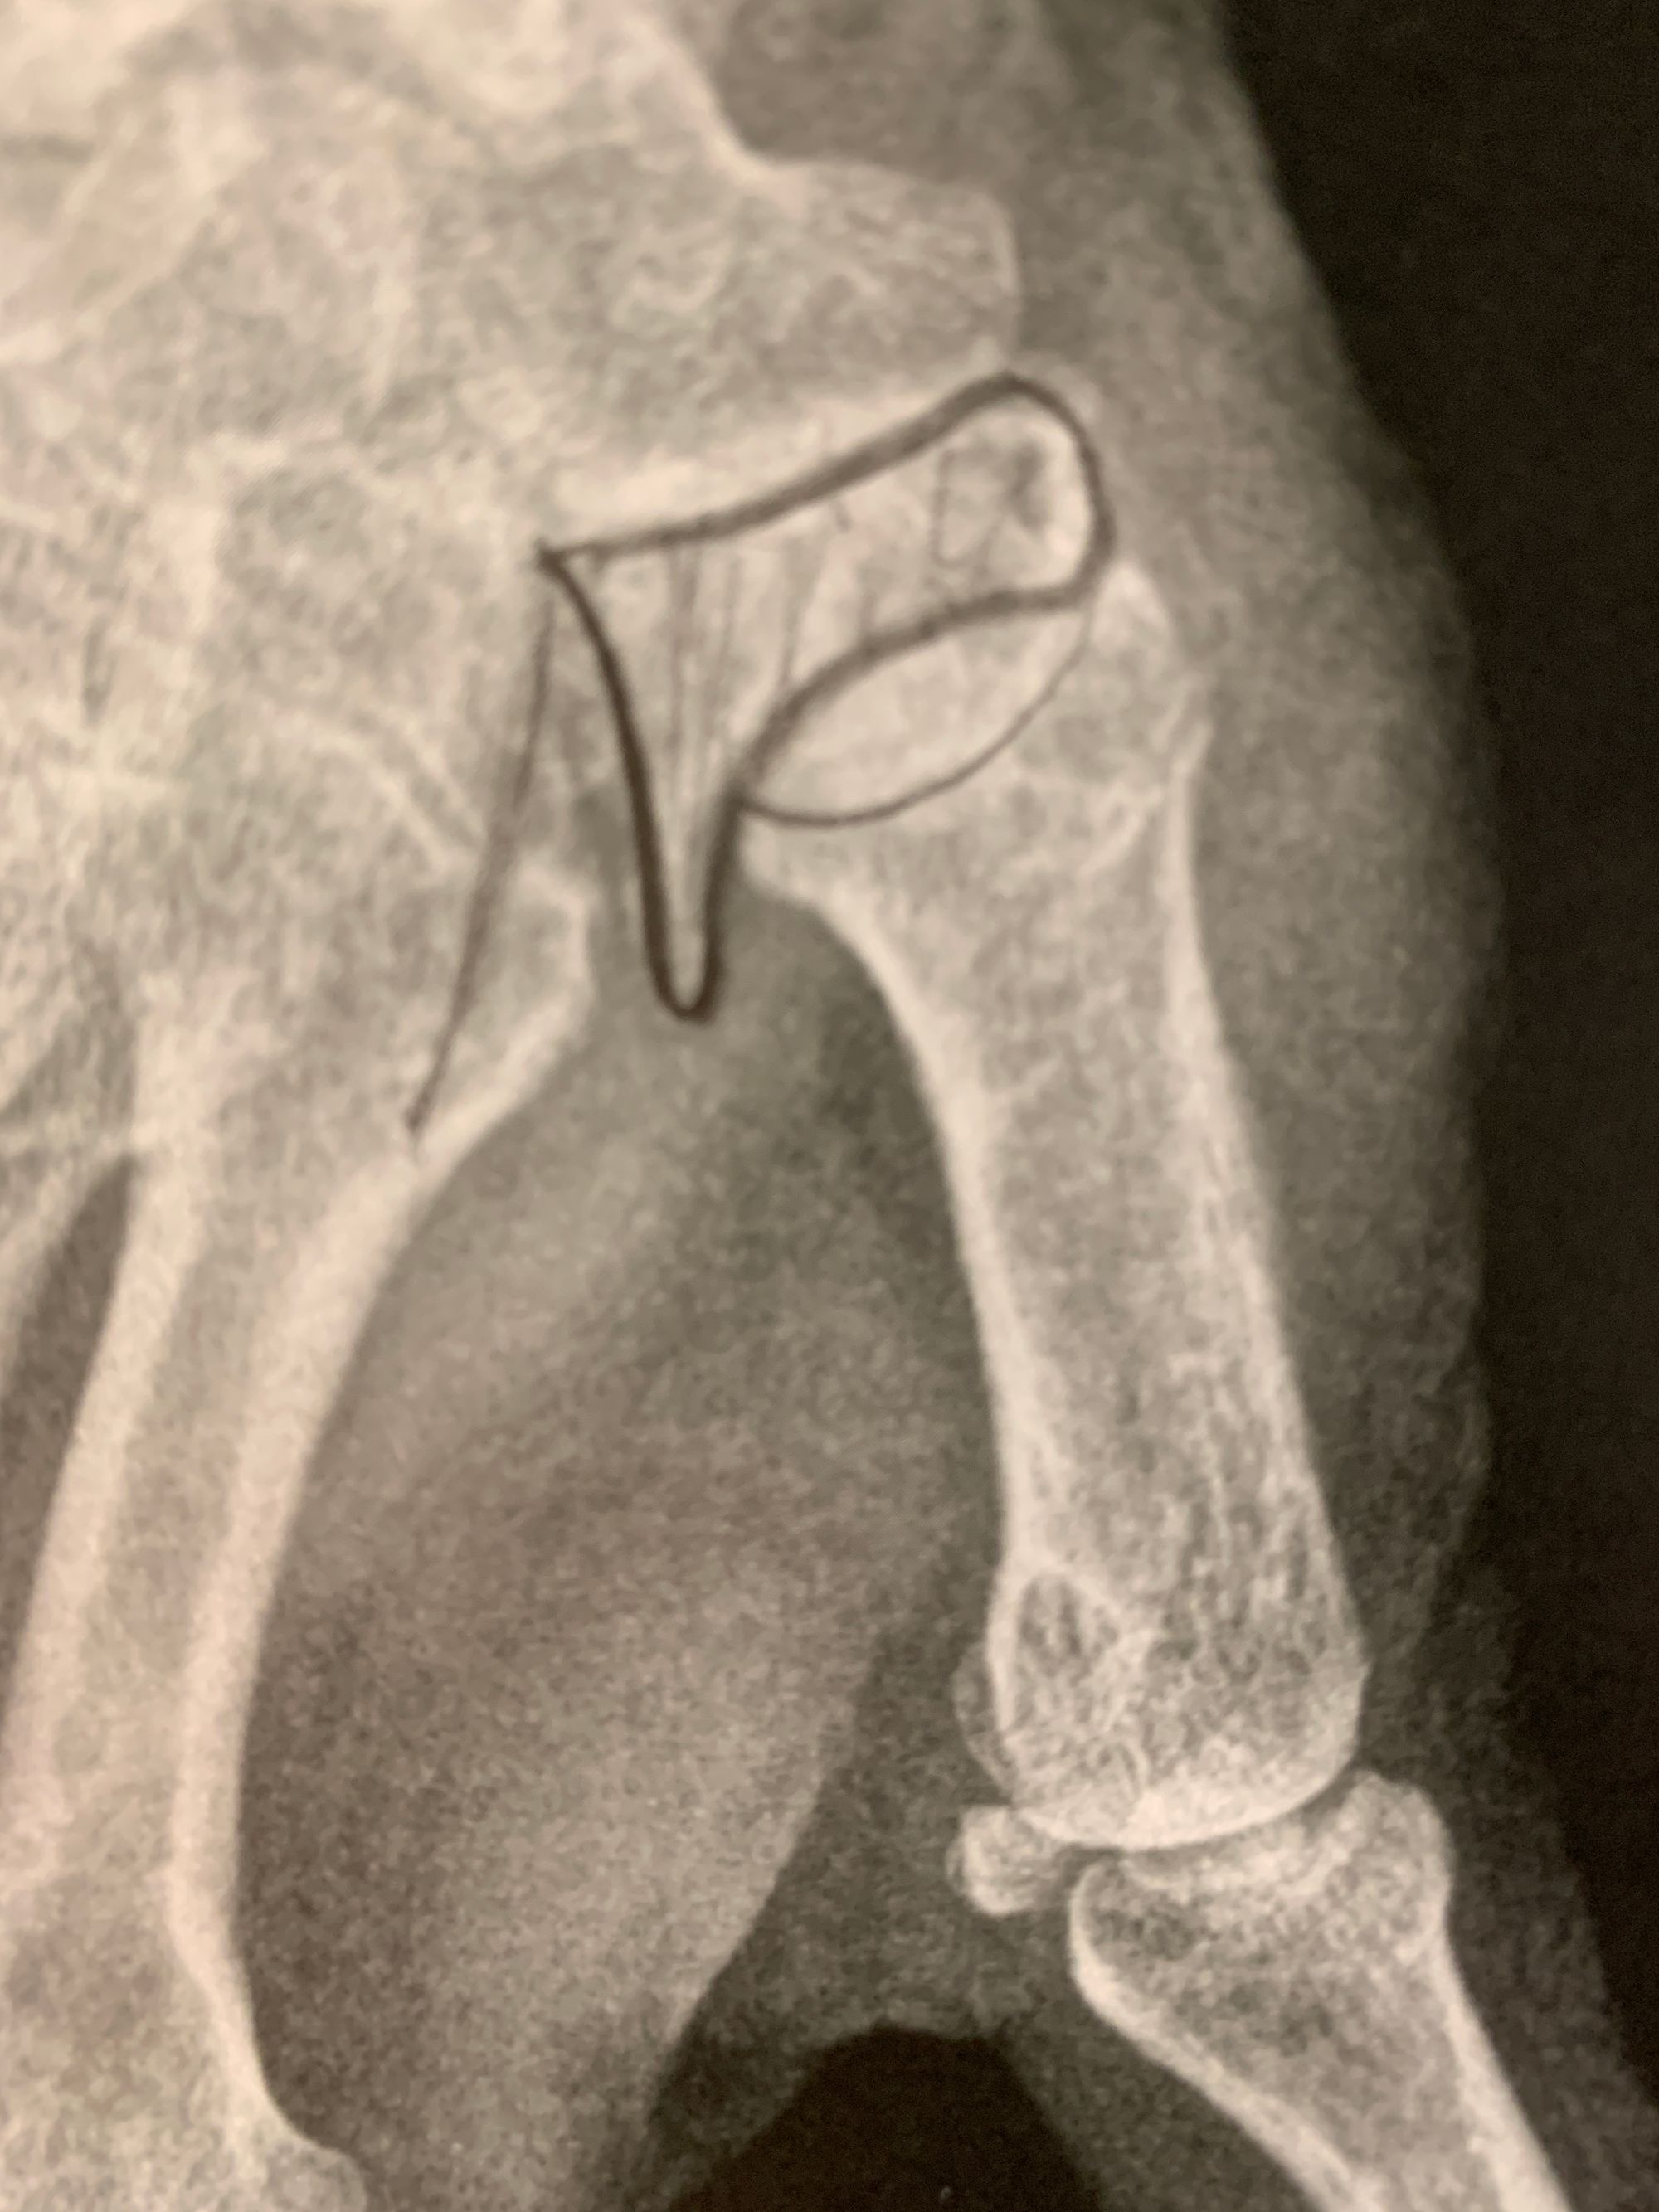

The usual standard treatment is STT arthrodesis. This procedure has been widely tested and there are rarely any complications, and even non-union does not cause pain for a large majority of cases. Figure 5.

In fact, the patient is usually more bothered by the osteosynthesis material and can often ask for it to be removed. This is why my preferred technique is resurfacing the distal pole of scaphoid using an INCA™ prosthesis (Groupe Lepine). The procedure is quick and easy and can be performed through an anterior portal. The outcomes are good, with mild or zero pain and good finger opposition. Figure 6.

The other option is a distal scaphoid excision with tendon interposition (FRC strip), although I tend to use this as a revision solution following failure of a primary INCA arthroplasty. Figure 7.